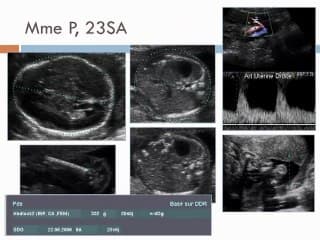

L'auteur contrairement à l'intitulé présente une belle observation d'une lissencéphalie avec une vallée sylvienne restant anormalement ouverte et qui a présenté l'intérêt d'attirer l'attention sur le développement anormal du cerveau fœtal. Introduction pédagogique dans le cadre difficile des lissencéphalies avec des étiologies complexes comme les mutations génétiques ou les infections à CMV.